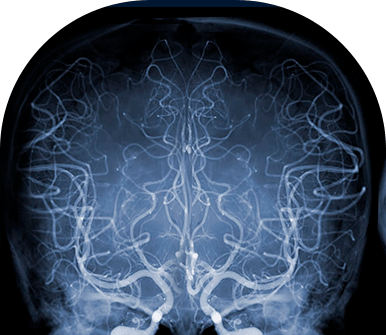

Angiografia

A angiografia é um exame realizado para visualizar o interior dos vasos sanguíneos. Ela permite detectar aneurismas, coágulos, dissecções arteriais, malformações arteriovenosas e tumores, entre outras demandas.

O exame é feito com a utilização de contraste iodado, injetado em uma artéria ou veia que vasculariza o cérebro e a medula espinhal a partir de um cateter endovascular.